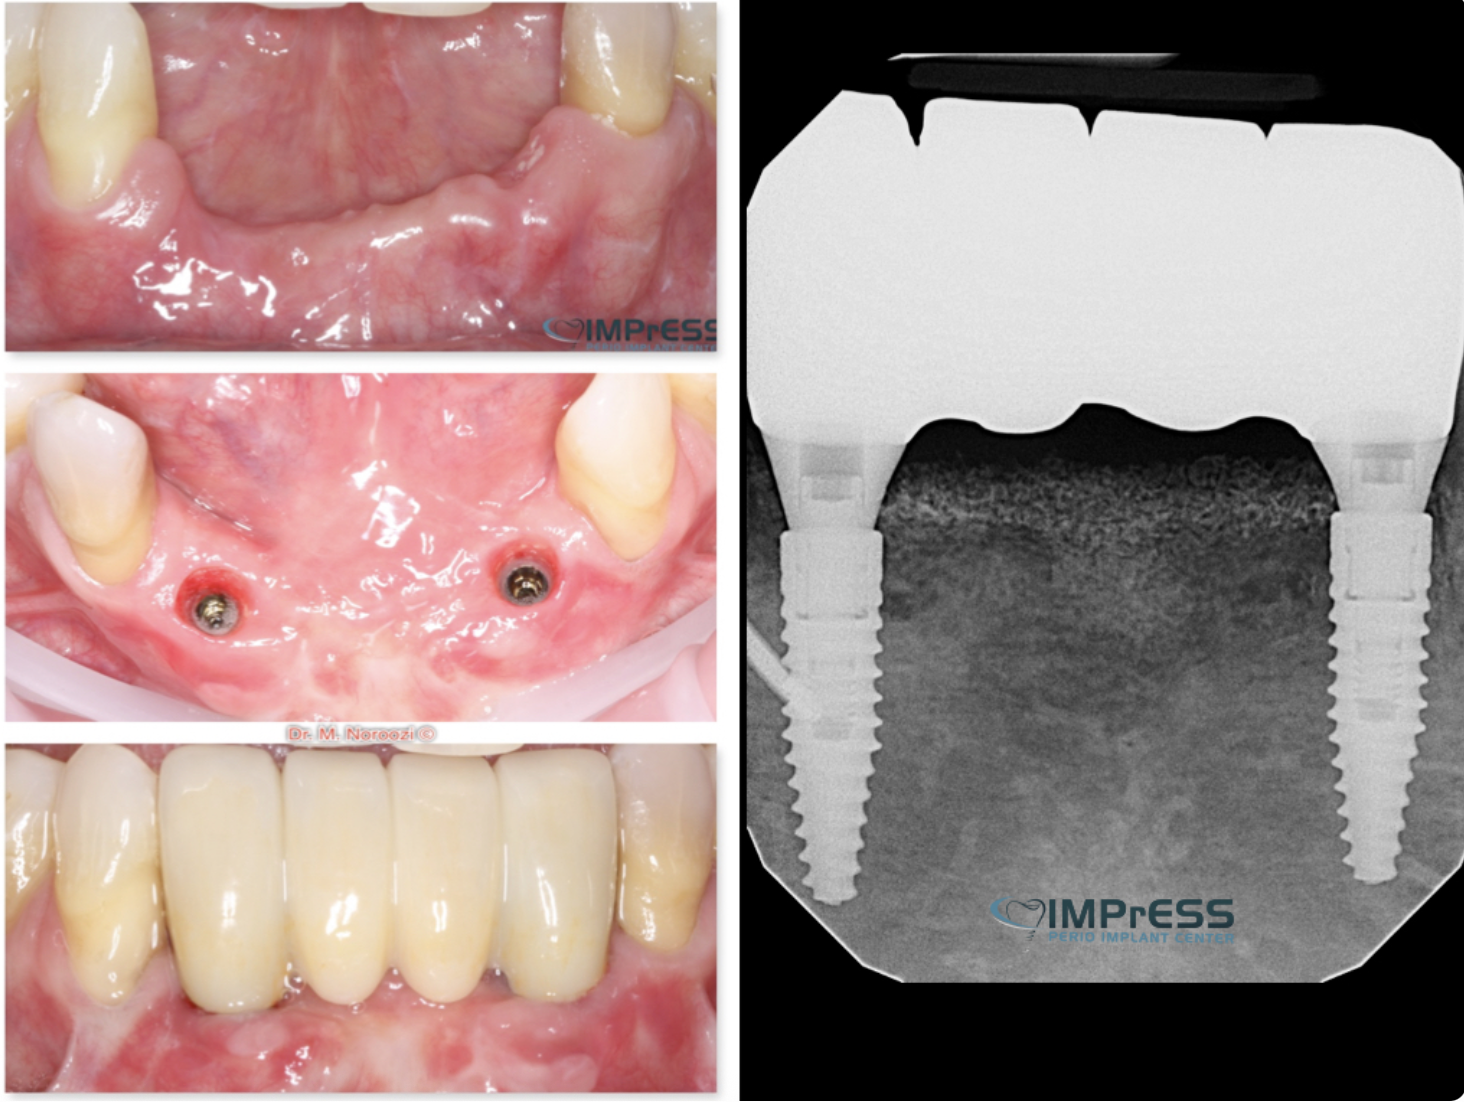

Before & Afters of Dental Implant Patients

Complete Dental Implant Cases Gallery

• When replacing several teeth or all of your teeth, a fixed bridge is anchored to your dental implants. A bridge is a dental restoration that replaces one or more missing teeth by spanning an area that has no teeth. The bridge is held firmly in place by dental implants on each side of the missing tooth or teeth.

Dental implant treatment is sometimes a team effort between your periodontist and a restorative dentist.  Dr. Noroozi  at IMPrESS Perio Implant Center located in Burnaby BC performs the actual implant surgery, initial tooth extractions, and bone and gum grafting if necessary.  The restorative dentist (your dentist) or our specialists (if you do not have a dentist) will fit and make the permanent prosthesis. Your dentist or our specialists will also make any temporary prosthesis needed during the implant process.

General Disclaimer: The results in the photographs are examples only and do not imply any certainty of the result of a procedure, and all outcomes are subject to the circumstances of the individual patient.